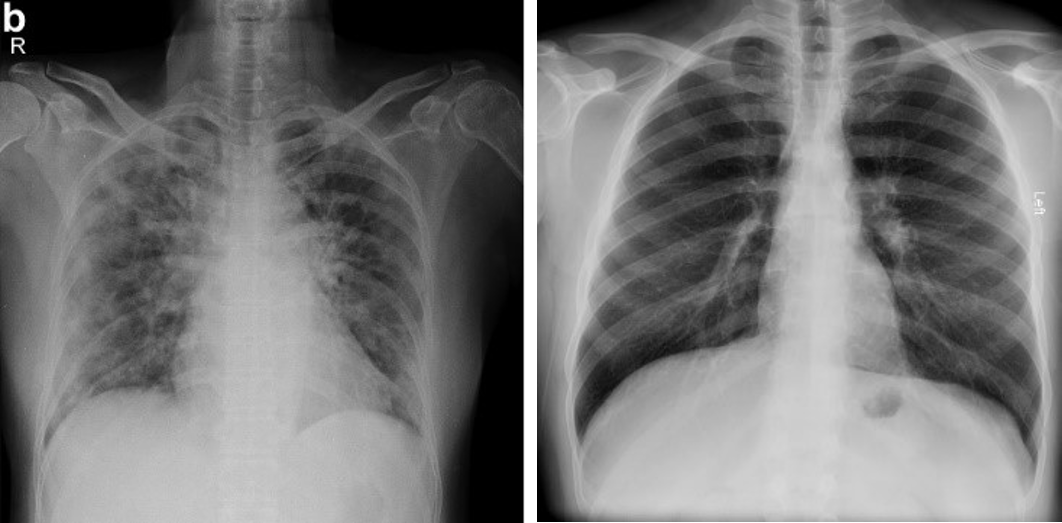

From a pictorial perspective of radiological images, CXR is the less sensitive modality with ground glass densities (GGO) easily detectable on CT but not CXR; CXR densities often appear hazy while CT densities have a clear contrast. However, reticular opacities are often more apparent on CXR than on CT. On baseline CXR, consolidations are the most common finding, with COVID-19 and viral pneumonia producing lung opacities in multiple lobes as opposed to one in bacterial pneumonia which tends to be unilateral. COVID-19 pneumonia has prominent peripheral air space opacities which are readily identified by both CT and CXR with CT reporting peripheral lung distribution in 33-86% of cases [4, 5]. Diffuse air space diseases such as acute respiratory distress syndrome (ARDS) demonstrate similar patterns to CXR, but these COVID-19 lung opacities rapidly evolve into a diffuse coalescent or consolidative pattern with 1-3 weeks of symptom onset [6, 7]. One study reported that of 64 patients, consolidation was found in (30/64, 47%) of patients while GGO was found in (21/64, 33%). Common distribution locations included peripheral (26/64, 41%) and lower zone (32/64, 50%), with most showing bilateral involvement (32/64, 50%) [1]. Although very uncommon, pleural effusions were found in a small number of cases.

In this study, 261 COVID-19 chest X-ray images have been obtained from the open-source COVID-19-CT-CXR dataset [9]. These images were extracted from figures, associated captions, and subfigures in COVID-19 articles from the PubMed Central Open Access (PMC-OA) subset. Most figures found in the PMC-OA articles are compound figures, each consisting of several subfigures often being of multiple categories such as CT, CXR, or an assortment of 26 other scientific figures. A deep-learning model was designed to distinguish compound figures from other figure types [9]. The designed deep-learning model is a convolutional neural network pretrained on the ImageCLEF Medical dataset [10].